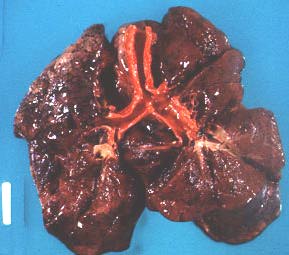

Right main bronchus is longer and more in line with the trachea (gross photograph, posterior view).